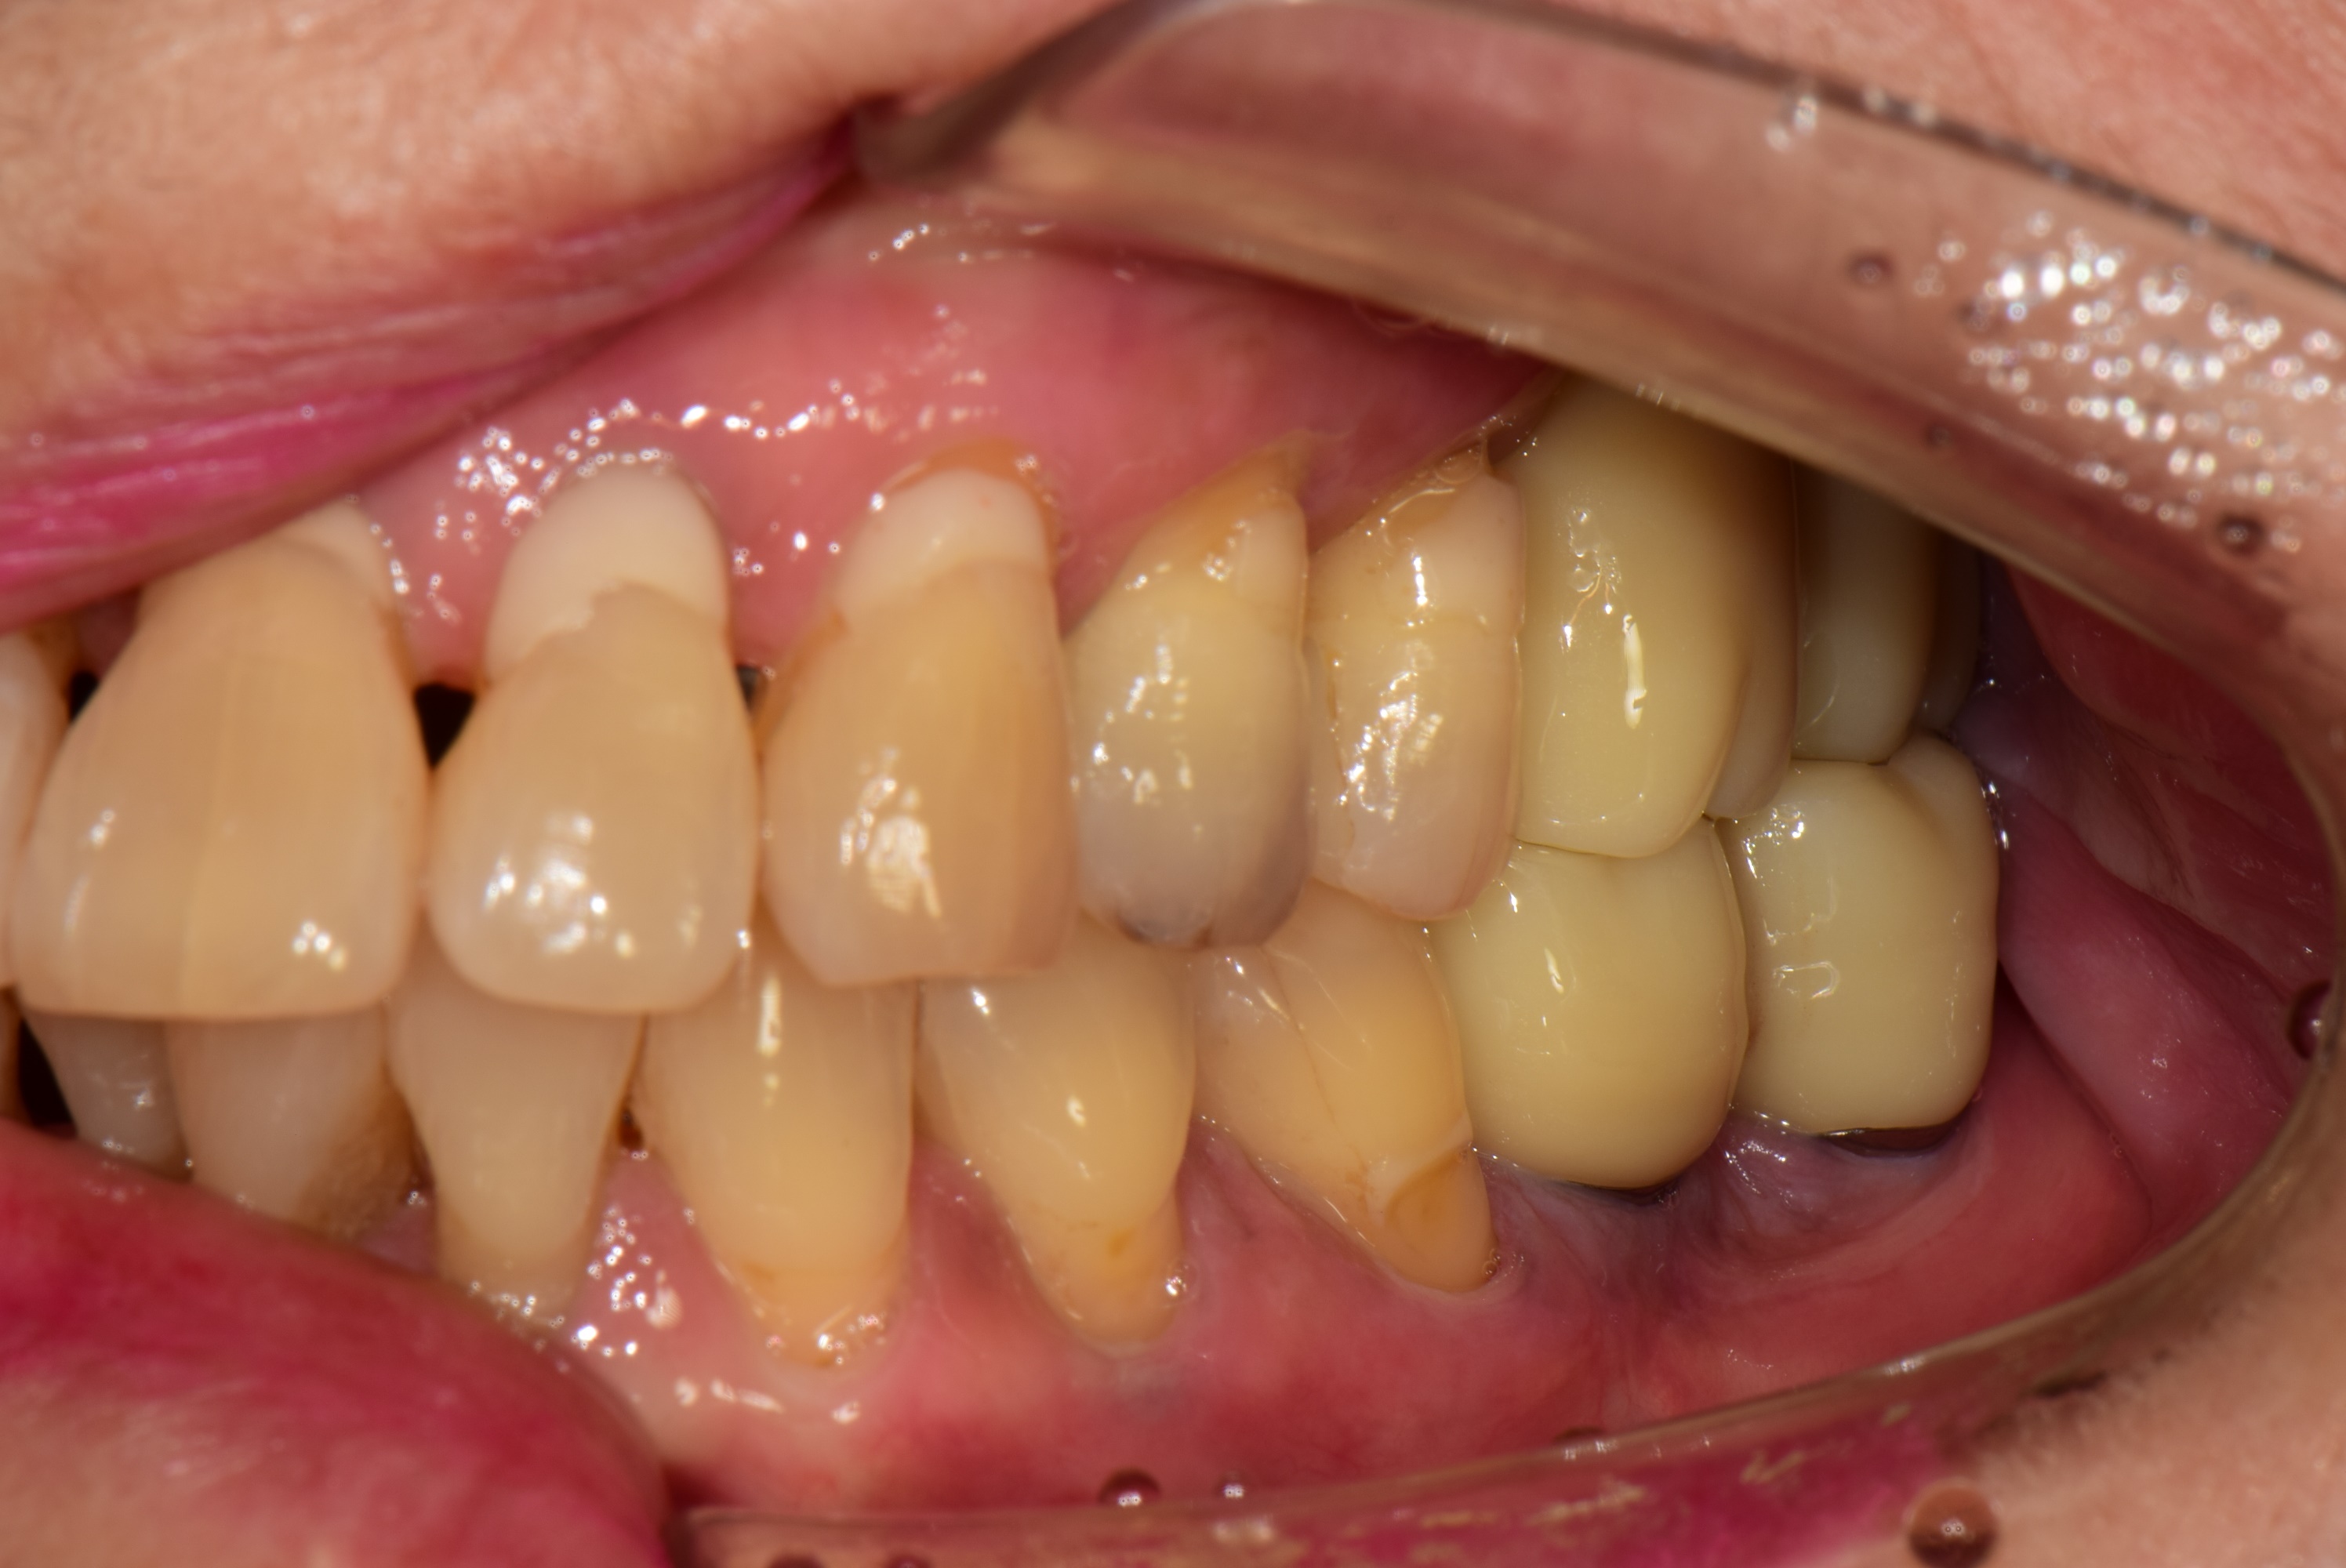

오랜 기간 아래 어금니가 없이 지내셨던 50대 여성분이 김포 서울케이치과에 내원 하셨습니다.

검진을 해보니 위에 양쪽 어금니가 많이 내려와 있고 치주염이 심하여 흔들리고 있었습니다.

치아를 살리기에는 이미 늦은 상태로 발치 후 임플란트로 치료 계획을 세웠습니다.

<처음 상태>

파노라마 엑스레이와 구내 사진에서 보듯이 위에 양쪽 어금니는 모두 발치가 필요한 상태입니다.

<치료계획>

오른쪽(사진상 왼쪽) 위 4개의 어금니 발치 후 3개 임플란트 식립

왼쪽 위(사진상 오른쪽) 위 2개의 어금니 발치 후 2개 임플란트 식립

왼쪽 아래 2개의 임플란트 식립.

모든 임플란트는 네비게이션을 이용하여 식립했습니다.